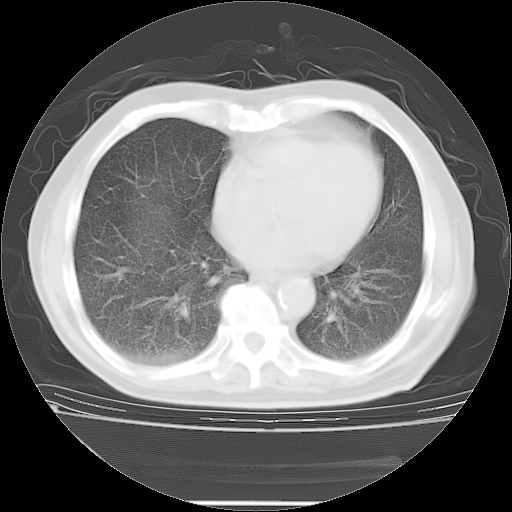

今天复查肺部CT,发现双肺广泛磨玻璃样改变。所以我把3月19日和5月9日相隔50天的肺部CT上传。请大家会诊。

2009年3月19日肺部CT片。

2009年3月19日肺部CT